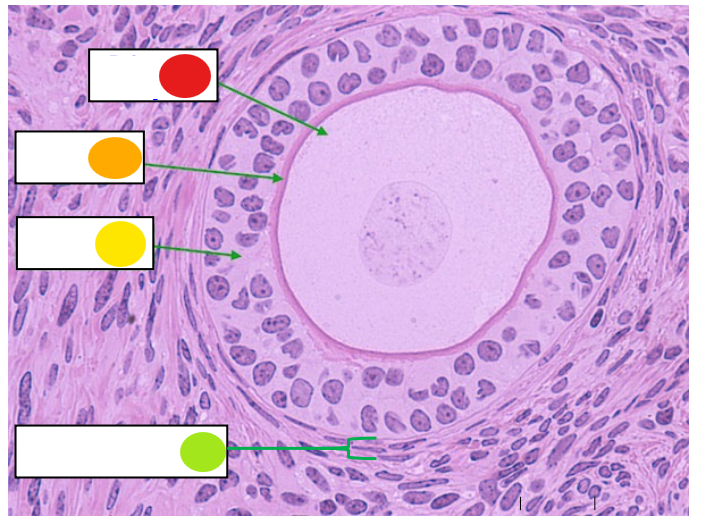

red

granulosa cells

orange

thecal cells

yellow

primary or secondary oocyte

light green

cumulus oophorus

dark green

antrum

what is this

tertiary follicle